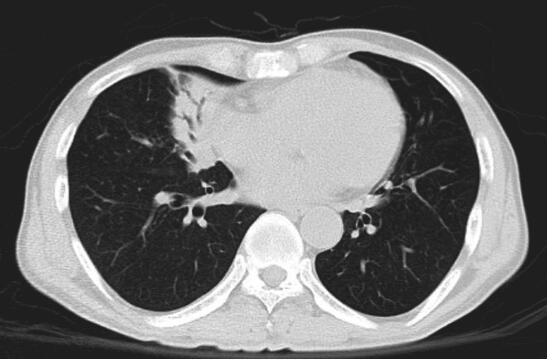

入院后给予亚胺培南西司他汀2.0g/d,静脉滴注治疗,患者体温降低,维持在37.5℃左右,咳嗽、咳痰等症状好转。血培养见放线菌。CT引导下经皮肺穿刺活检病理找到菌丝及孢子,拟诊真菌。2013年12月18日胸部CT示:右肺中叶大片高密度影,伴空气支气管征(图1)。

图1 2013年12月18日胸部CT

右肺中叶大片高密度影,伴空气支气管征

2. 主要表现为发热,咳嗽。查体右中下肺可闻及湿啰音,胸部CT右肺中叶大片高密度影,伴空气支气管征。

肺放线菌诊断的主要方法为支气管镜、经皮肺穿刺或外科手术切除活检病理诊断,有少数报道为痰涂片和胸腔积液中找到放线菌。肺放线菌病的影像学表现无特异性,可表现为实质性团块影、片状影、结节、支气管充气征、空洞、胸腔积液、纵隔淋巴结肿大及胸膜增厚,病变部位以左下叶居多,可能与吸入途径感染有关;右中叶次之。目前,罕见报道肺放线菌病PET表现,2012年欧洲胸部影像学年会报告显示病灶18F-FDG摄取值增高,SUV平均为(5.73±2.74),与肺癌难以鉴别。